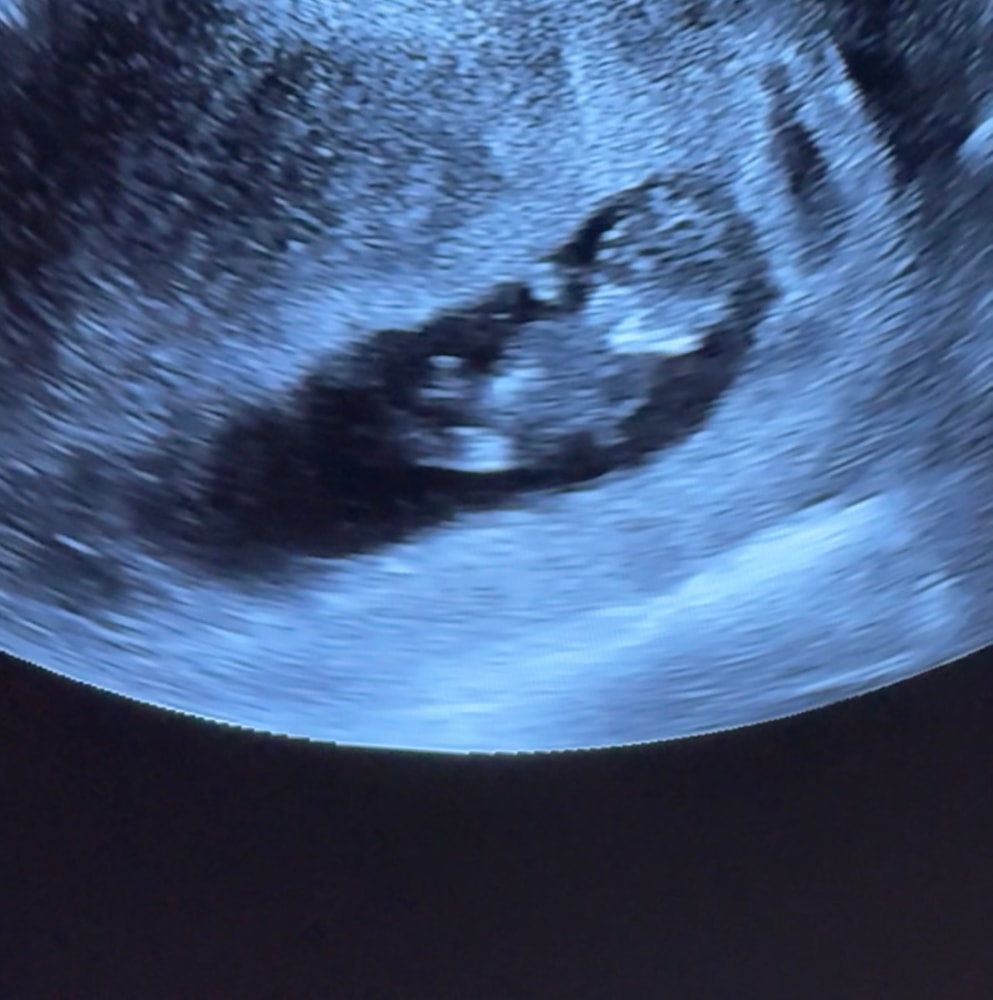

УЗИ на 11 й недельке

решили сходить, проверить ,как там наша Ляля ,а там уже человек с ручками и ножками 🥰🥰🥰🥰🥰так интересно кто )))

Марина, и так и так ,этот снимок с трансвагинальным датчиком